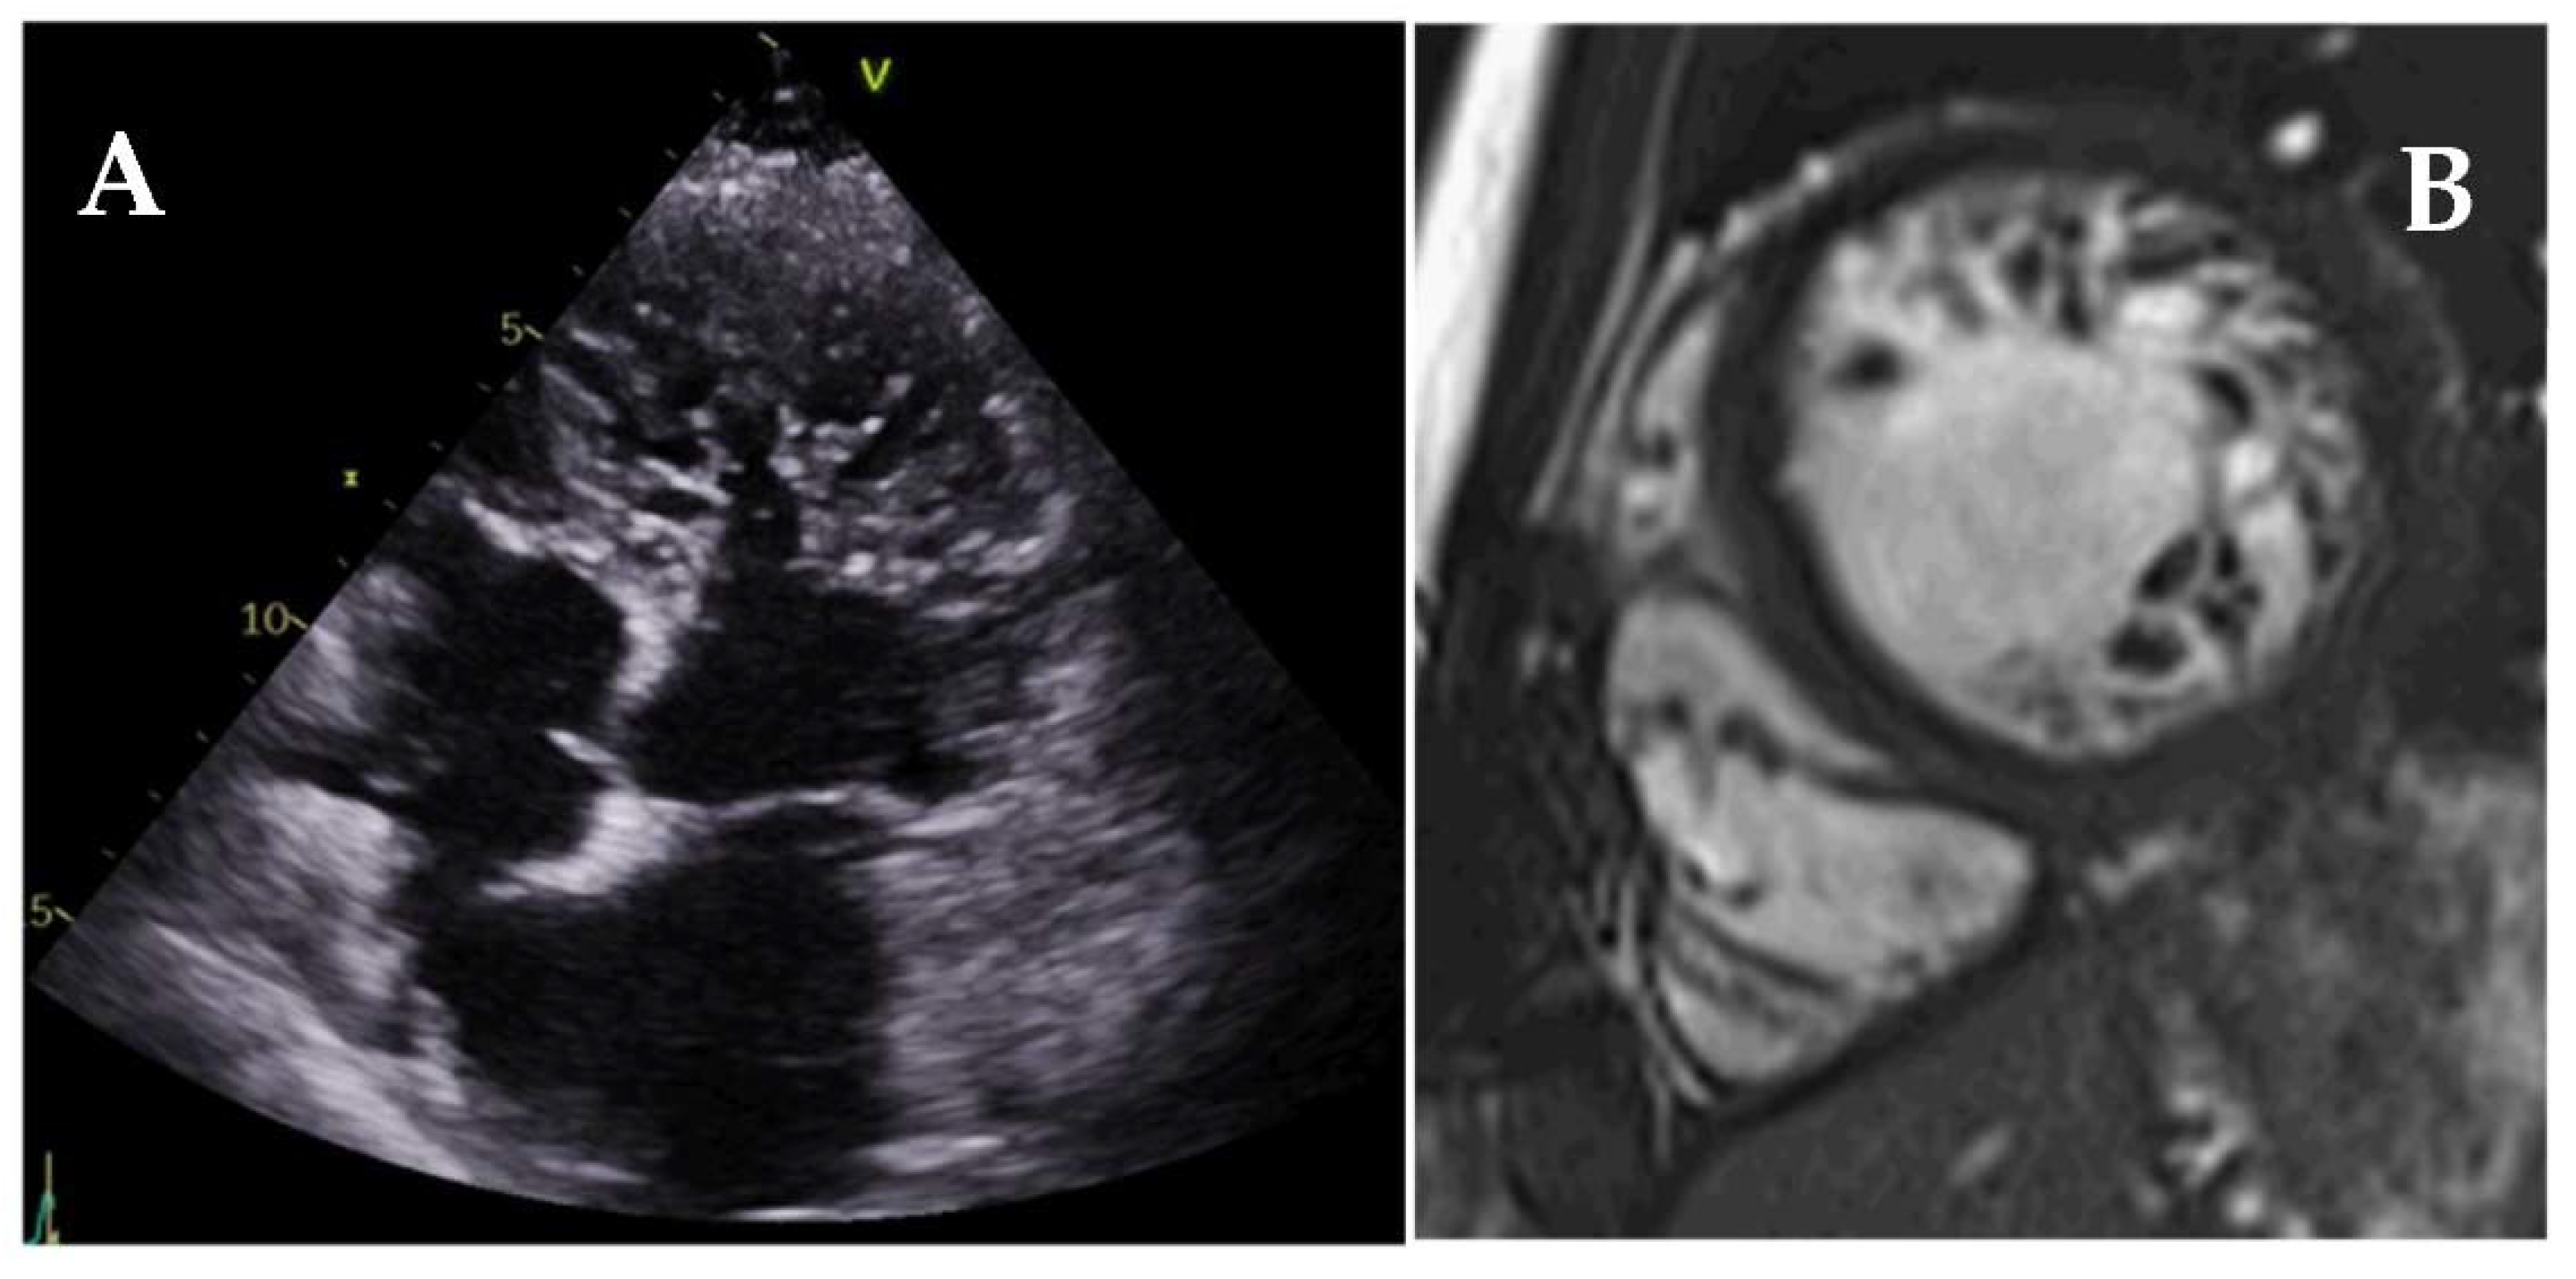

6. Left Ventricular Noncompaction

- Towbin, J.A.; Lorts, A.; Lynn, J. Left ventricular non-compaction cardiomyopathy. Lancet 2015, 22, 813–825. [Google Scholar] [CrossRef]

- Chin, T.K.; Perloff, J.K.; Williams, R.G.; Jue, K.; Mohrmann, R. Isolated noncompaction of left ventricular myocardium. A study of eight cases. Circulation 1990, 82, 507–513. [Google Scholar] [CrossRef] [Green Version]

- Oechslin, E.N.; Attenhofer Jost, C.H.; Rojas, J.R.; Kaufmann, P.A.; Jenni, R. Long-term follow-up of 34 adults with isolated left ventricular noncompaction: A distinct cardiomyopathy with poor prognosis. J. Am. Coll. Cardiol. 2000, 36, 493–500. [Google Scholar] [CrossRef] [Green Version]

- Petersen, S.E.; Selvanayagam, J.B.; Wiesmann, F.; Robson, M.D.; Francis, J.M.; Anderson, R.H.; Watkins, H.; Neubauer, S. Left Ventricular Non-Compaction: Insights From Cardiovascular Magnetic Resonance Imaging. J. Am. Coll. Cardiol. 2005, 46, 101–105. [Google Scholar] [CrossRef] [PubMed] [Green Version]

- Bellavia, D.I.; Michelena, H.; Martinez, M.; Pellikka, P.; Bruce, C.J.; Connolly, H.M.; Villarraga, H.R.; Veress, G.; Oh, J.K.; Miller, F. Speckle myocardial imaging modalities for early detection of myocardial impairment in isolated left ventricular non-compaction. Heart 2009, 96, 440–447. [Google Scholar] [CrossRef]

- Tarando, F.; Coisne, D.; Galli, E.; Rousseau, C.; Viera, F.; Bosseau, C.; Habib, G.; Lederlin, M.; Schnell, F.; Donal, E. Left ventricular non-compaction and idiopathic dilated cardiomyopathy: The significant diagnostic value of longitudinal strain. Int. J. Cardiovasc. Imaging 2016, 33, 83–95. [Google Scholar] [CrossRef]